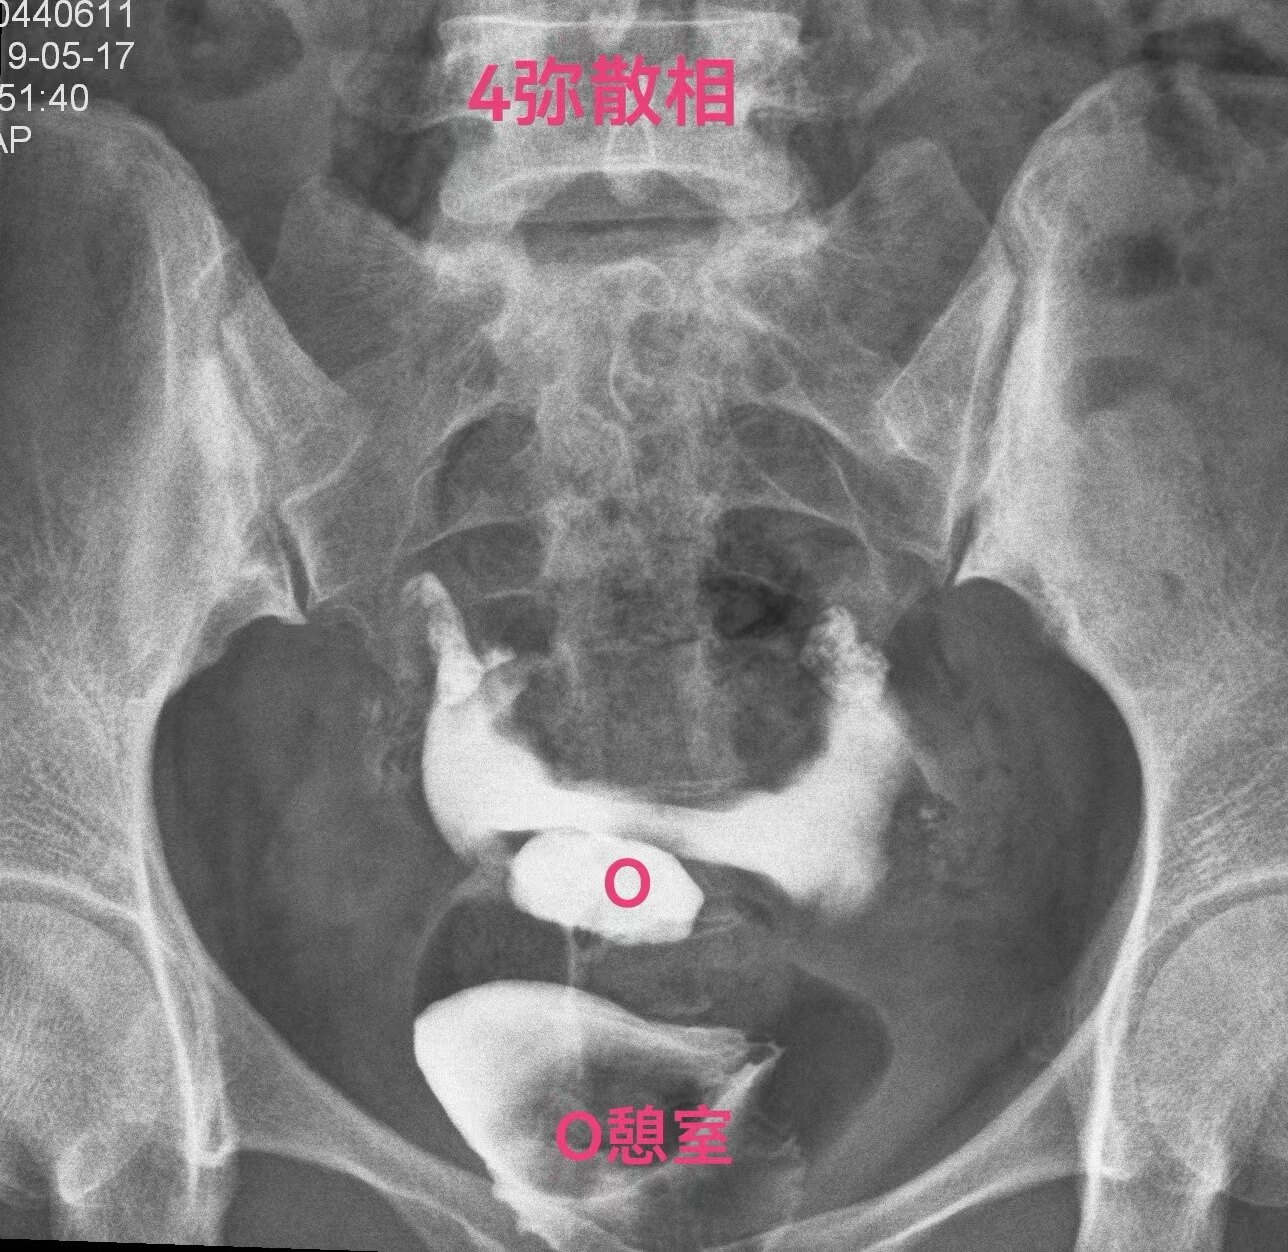

下面一例造影图就可以看直观看懂憩室导致经血流出不畅

4(1).jpg

弥散相子宫腔内造影剂完全流出来了,憩室内还有较多造影剂充满憩室腔。月经血流出相仿。